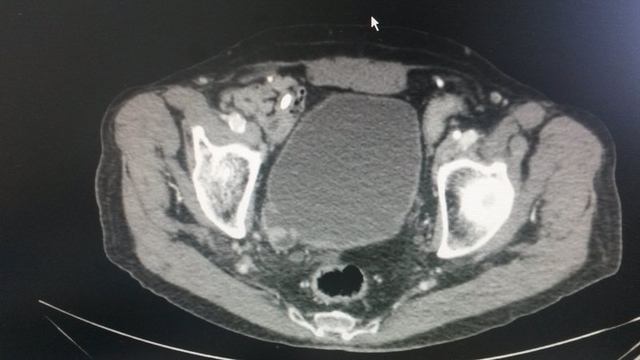

• TAC abdomino-pélvico

TAC abdomino-pélvico

Lesión excrecente de 17x12 mm en divertículo postero-lateral derecho de vejiga